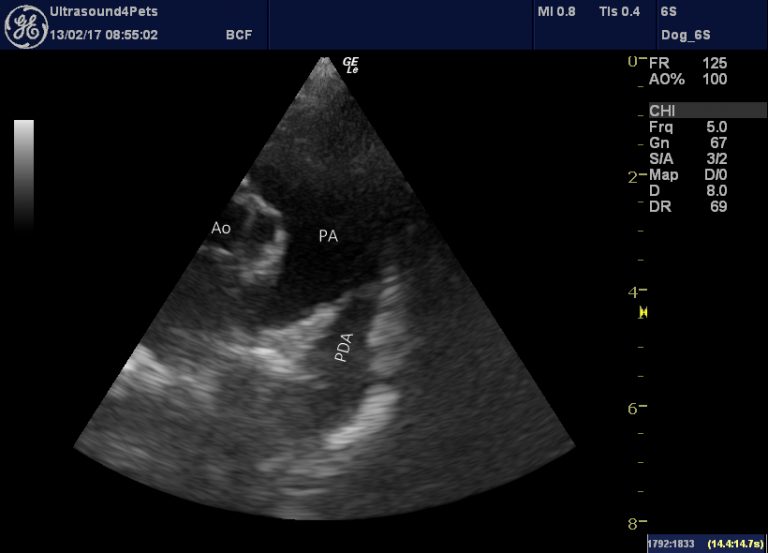

From www.vetpracticesupport.com

PDA with pulmonary hypertension in an adult dog difficult decision What Is A Pda In A Dog The breeds that pda most commonly affects are collie, miniature poodle, shetland. Patent ductus arteriosus (pda) is a common congenital heart defect in the dog.1, 2 considerable variability in pda anatomy occurs. Patent ductus arteriosus in dogs is a congenital heart disease that can be fatal. Persistent flow through the ductus leads to excess blood flow (volume. It is caused. What Is A Pda In A Dog.